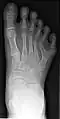

Полидактили́я (др.-греч. πολύς — много + δάκτυλος — палец, синоним — многопалость), также известная как гипердактилия — порок развития, характеризующейся бо́льшим, чем в норме, количеством пальцев на руках или ногах у человека, собак, котов и лошадей. Противоположным отклонением является олигодактилия.

У людей и животных она может проявляться как на одной, так и на обеих руках. Обычно дополнительный палец представляет собой небольшой кусочек мягкой ткани, которую можно удалить. Иногда это просто кость без суставов; очень редко лишний палец бывает полноценным. Дополнительный палец чаще всего образуется со стороны мизинца, реже - на стороне большого пальца и очень редко - между средними пальцами. Обычно лишний палец является аномальным разветвлением обычного пальца, редко возникает на запястье, как обычный палец.